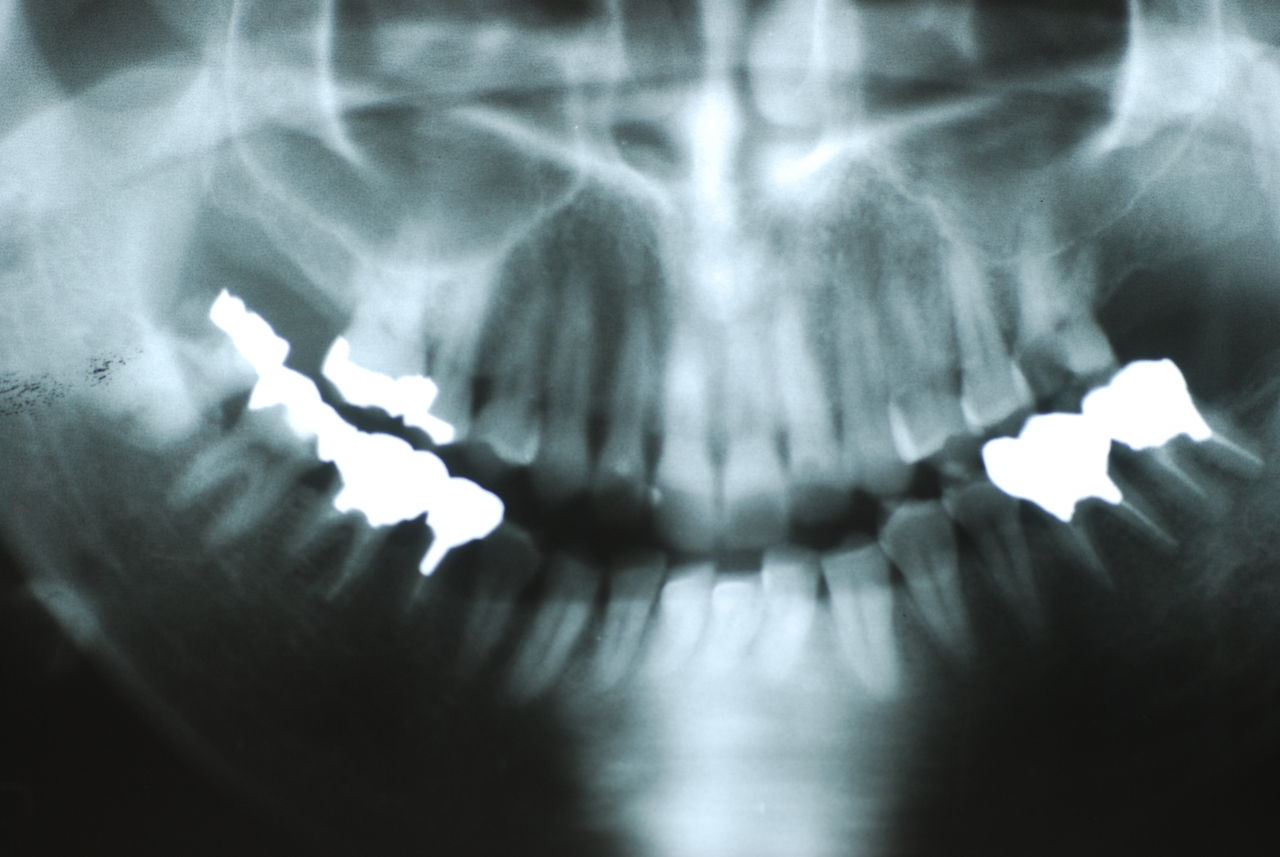

入れ歯の話から入りました。色々不満で注文があるようです。でも話が一段落して口腔内を調べると殆どの歯が重症で抜けそうな歯だらけなのです。

なぜ病気になるのかわからない方が多すぎます。歯が抜けるのは病気だからです。病気を治さずに何かお口の中に入れても土台である歯が抜けてしまっては同じことなのです。

何故歯が悪くなるのか、歯周病で抜けるのか分からなければ何を入れても歯は悪くなり抜けていくのです。

病気を治しましょう。それから差し歯や入れ歯を入れましょう!物を入れれば入れるほど、磨き方や掃除の仕方が上手にならなければ、すぐ抜けてくるのです。